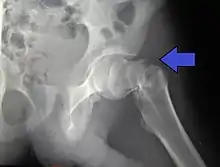

![]() | |

| Intertrochanteric hip fracture in a 17-year-old male | |